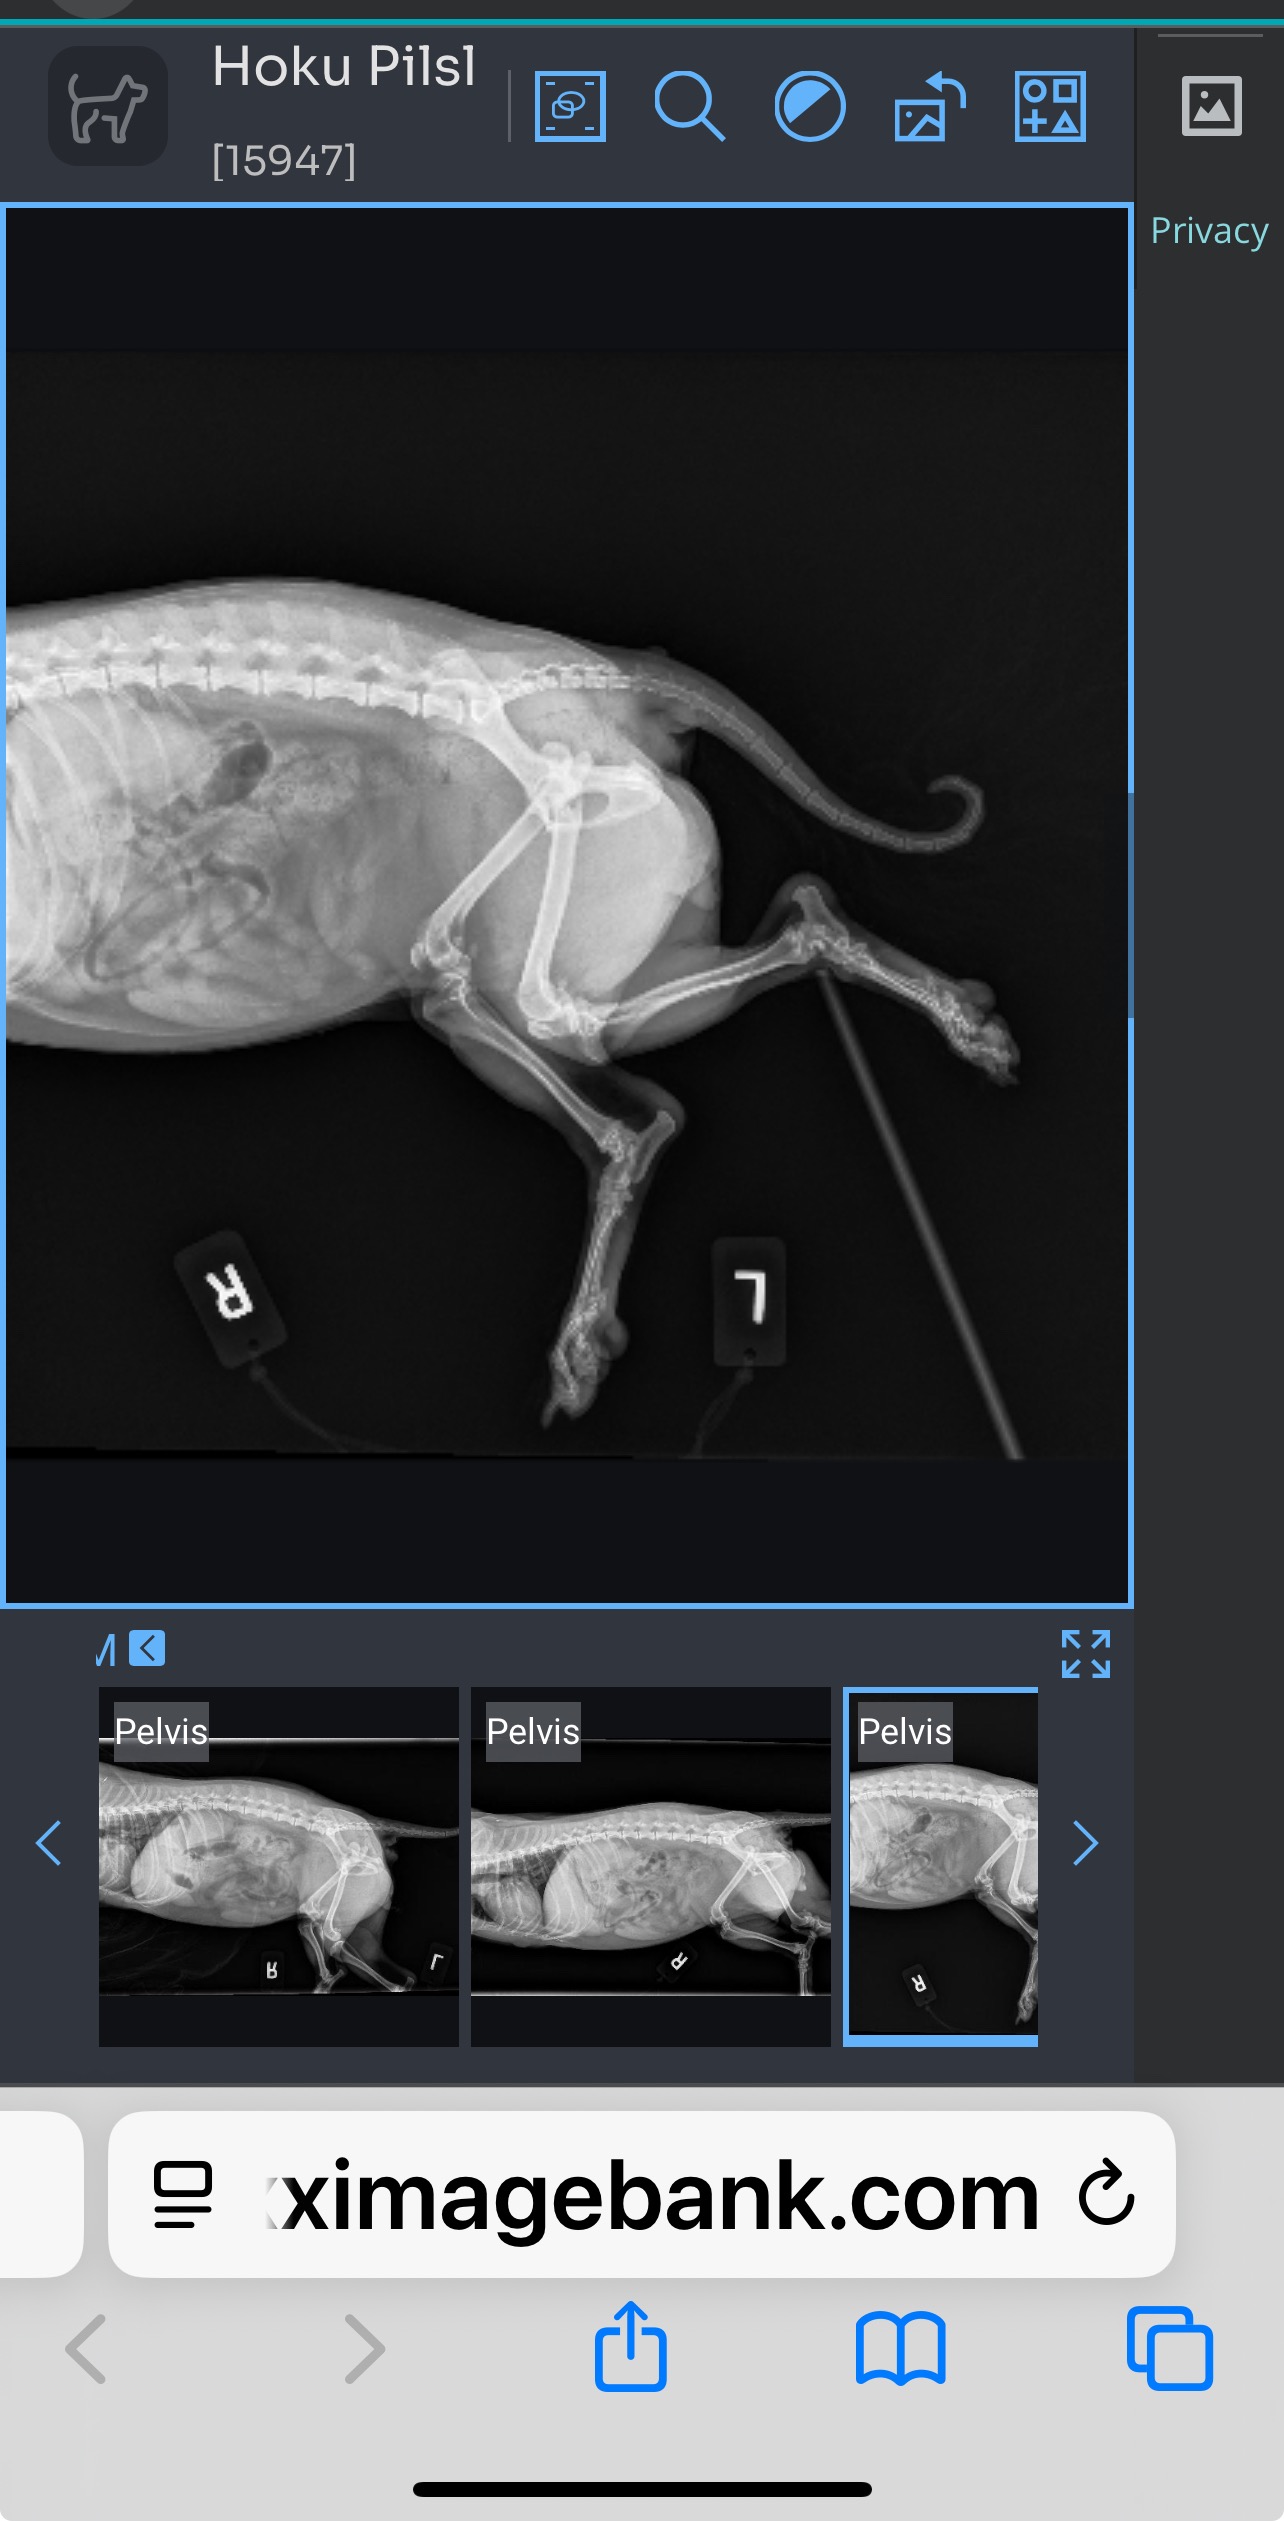

Our neighbor, who had just moved in, left her dog unleashed and her door open. Her dog ran out and attempted to aggressively attack Hoku. In the chaos, Hoku was badly hurt—her ligament ruptured and her hip was forced out of its socket. The pain was so intense that Hoku cried out for a long time until we could get her to the vet hospital. We immediately took her to the hospital, where she was sedated until we could get her to her primary veterinarian. Despite their best efforts, her hip wouldn’t stay in place because of the ruptured ligament. Now, Hoku is paralyzed and can barely walk. The neighbor initially offered to help, but later wished us luck and stepped away from the situation, leaving us to face this alone.

Our neighbor, who had just moved in, left her dog unleashed and her door open. Her dog ran out and attempted to aggressively attack Hoku. In the chaos, Hoku was badly hurt—her ligament ruptured and her hip was forced out of its socket. The pain was so intense that Hoku cried out for a long time until we could get her to the vet hospital. We immediately took her to the hospital, where she was sedated until we could get her to her primary veterinarian. Despite their best efforts, her hip wouldn’t stay in place because of the ruptured ligament. Now, Hoku is paralyzed and can barely walk. The neighbor initially offered to help, but later wished us luck and stepped away from the situation, leaving us to face this alone.